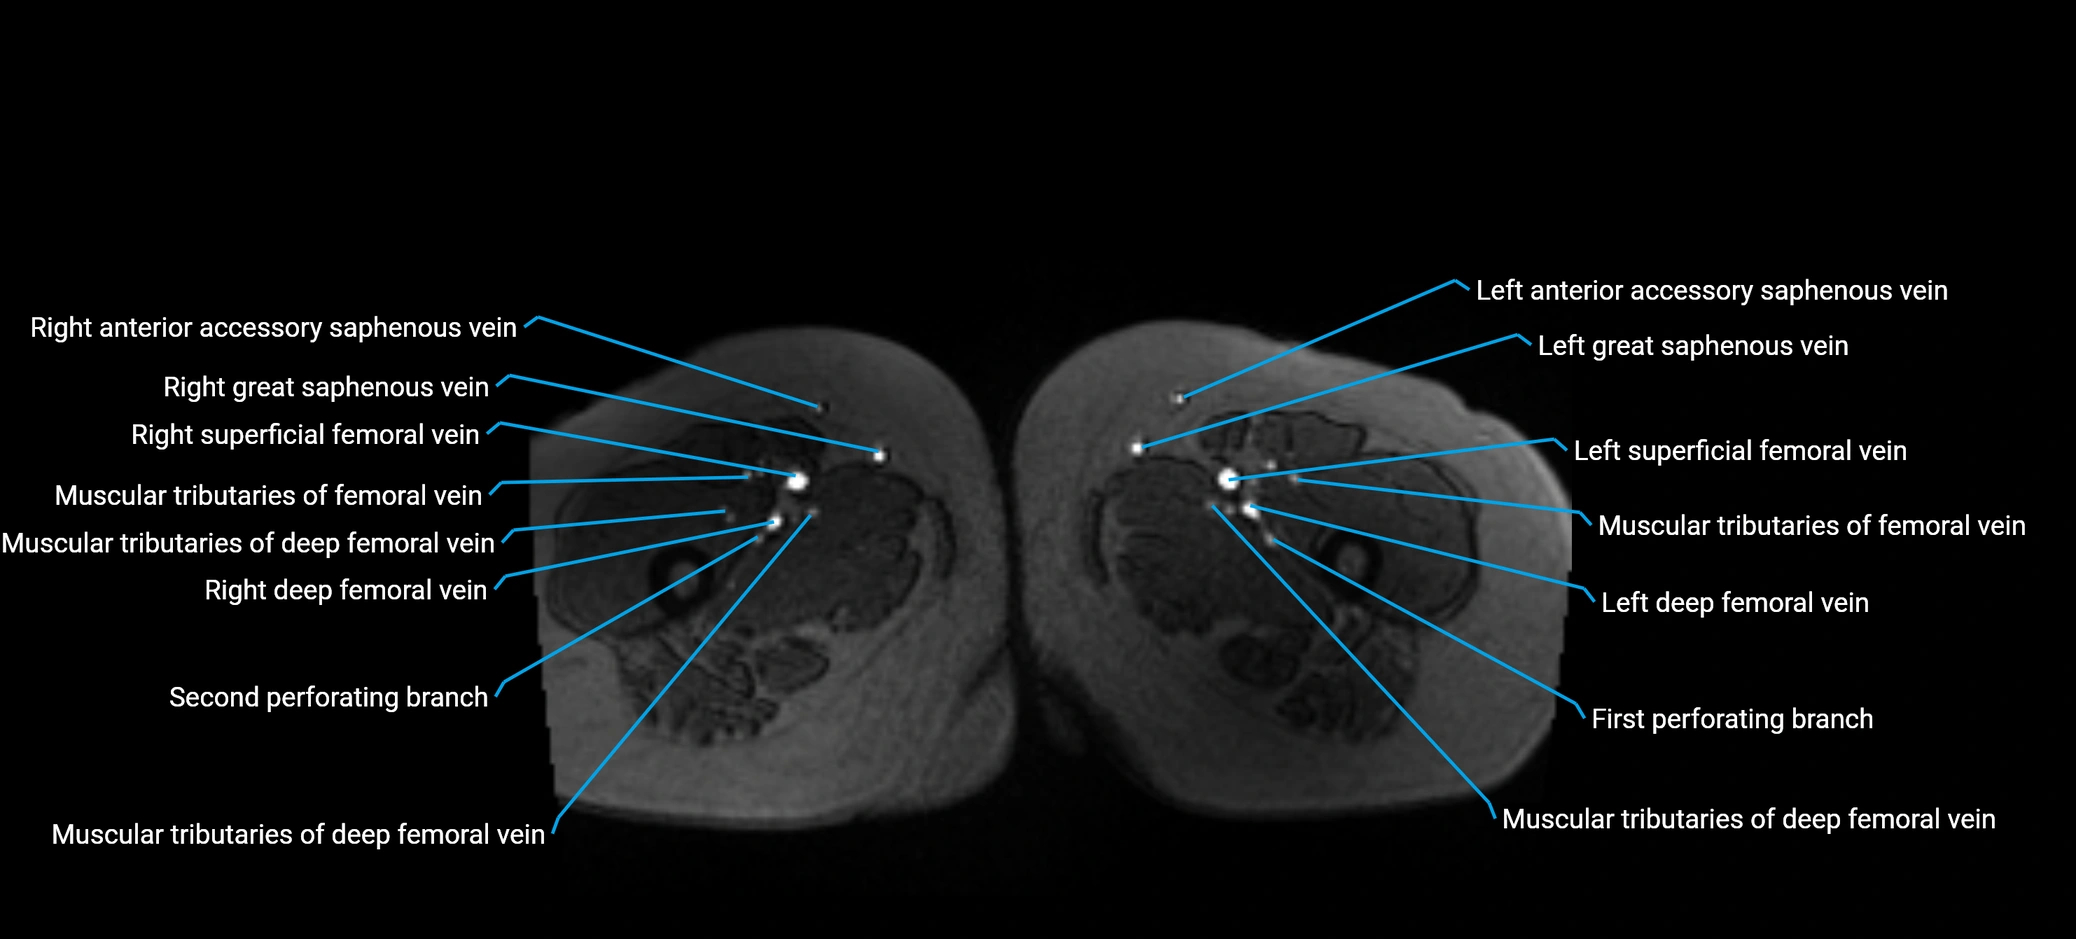

MRI image

image